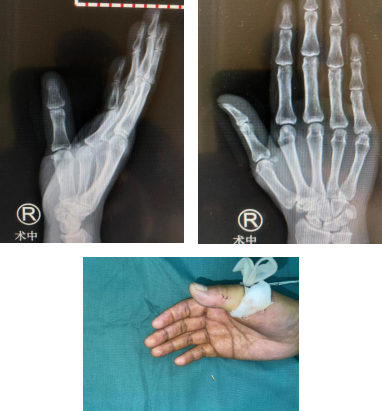

术后,异物取出

手术开始,熊医生手术团队术中仅做了一个不到1厘米的切口,顺利取出瓷片异物,术后复查右手X线,X线示:右拇指未见异物存留。术后第二天,王大姐非常激动地说: “非常感谢熊祖国医生高超的手术技术,这么小的切口也能完整的取出异物。”